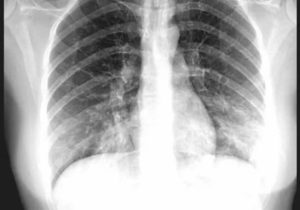

- Рентгенография грудной клетки – наиболее информативный способ выявление воспалительных процессов в легких (на снимках появляются характерные затемнения в местах поражения тканей и другие признаки заболевания);

Для постановки диагноза необходимо сделать рентгенограмму легких, а также сдать анализы крови и (при необходимости) мокроты. Кашель на ранних стадиях проявляется не у всех.

Пневмония очень опасна. Если ее не лечить, на поздних стадиях даже антибиотики не всегда могут с ней справиться. Если есть подозрения — сделайте рентген.